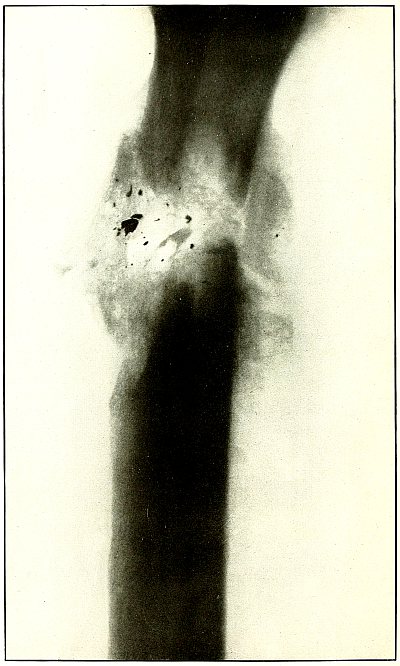

| 59. |

Gunshot wound, knee |

128 |

| 60. |